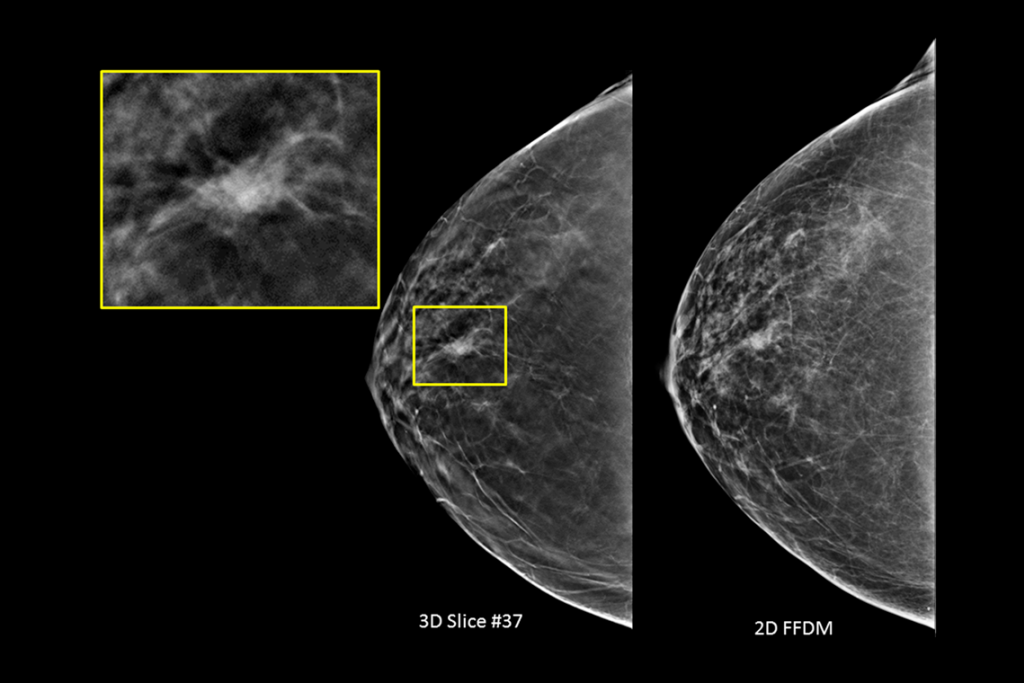

Clinical Images

Clinical images of breast scan mammography

Clinical images of breast scan with suspicious Lesion

Clinical images of breast scan